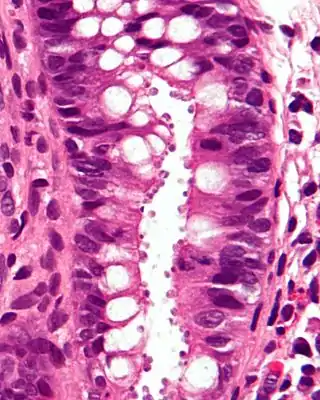

![]() Micrografía que muestra la criptosporidiosis. El Cryptosporidium son los cuerpos pequeños y redondos en la superficie del epitelio. Tinción H&E. Biopsia de colon. | ||